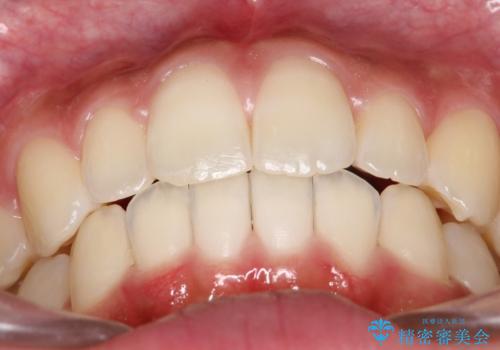

抜歯は行わず上顎の奥のスペースを利用して歯をスライドする方法の他に歯列弓の拡大やディスキング(歯と歯の間の隙間を作る処置)を行い叢生を改善しました。

歯の大きさの不揃いが原因の正中のズレは、ディスキング量を調整することで合わせています。

上の歯を後ろに送る方法として、歯茎に入れた小さなネジからゴムかけをして歯列全体を後ろに引っ張りました。

矯正装置としてはマウスピースを使用しています。

見た目、嚙み合わせ及び、治療期間や施術内容に大変ご満足いただきました。